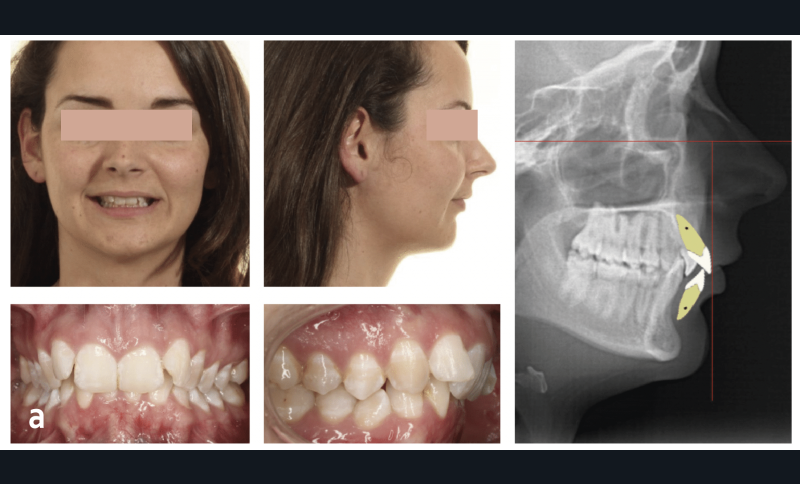

La céphalométrie aide au diagnostic. De manière simplifiée, sur une téléradiographie de profil, le plan de Francfort puis le plan antérieur de Cocconi, qui passe par le point le plus antérieur de l’os maxillaire, sont tracés ; la ligne qui passe par la face vestibulaire de l’incisive centrale maxillaire doit être tangente à ce plan (fig. 1). L’incisive centrale mandibulaire doit être au contact de son antagoniste. Si, à la suite de la simulation de cette analyse, l’incisive du bas est en dehors de l’enveloppe osseuse, cela implique le choix thérapeutique d’une chirurgie orthognatique du maxillaire et/ou de la mandibule (fig. 2).